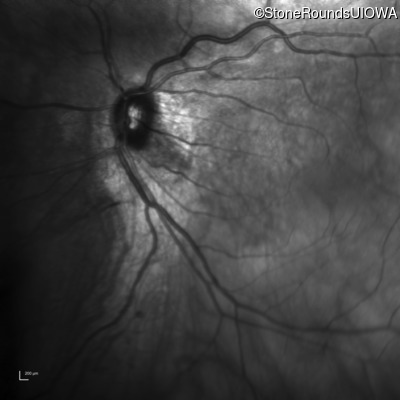

Infrared Fundus Photograph - Right - 20/40 +2

Exemplar